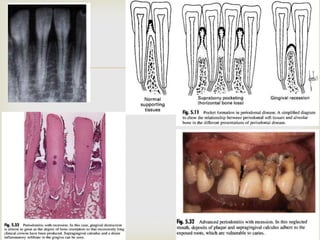

4. Advanced lesion: here the features are better described

clinically than histologically. Typically there is

 Periodontal pocket formation.

 Gingival ulceration and suppuration.

 Destruction of alveolar bone and periodontal ligament

 Tooth mobility, drifting and eventual tooth loss

Because the bone loss appears here, it is equated as

periodontitis.

The earlier lesions can be classified as gingivitis of

increasing severity.

The advanced lesion spreads apically, laterally around

the tooth and deep into the gum tissue papilla.

Bone resorption produces scarring and fibrous change.